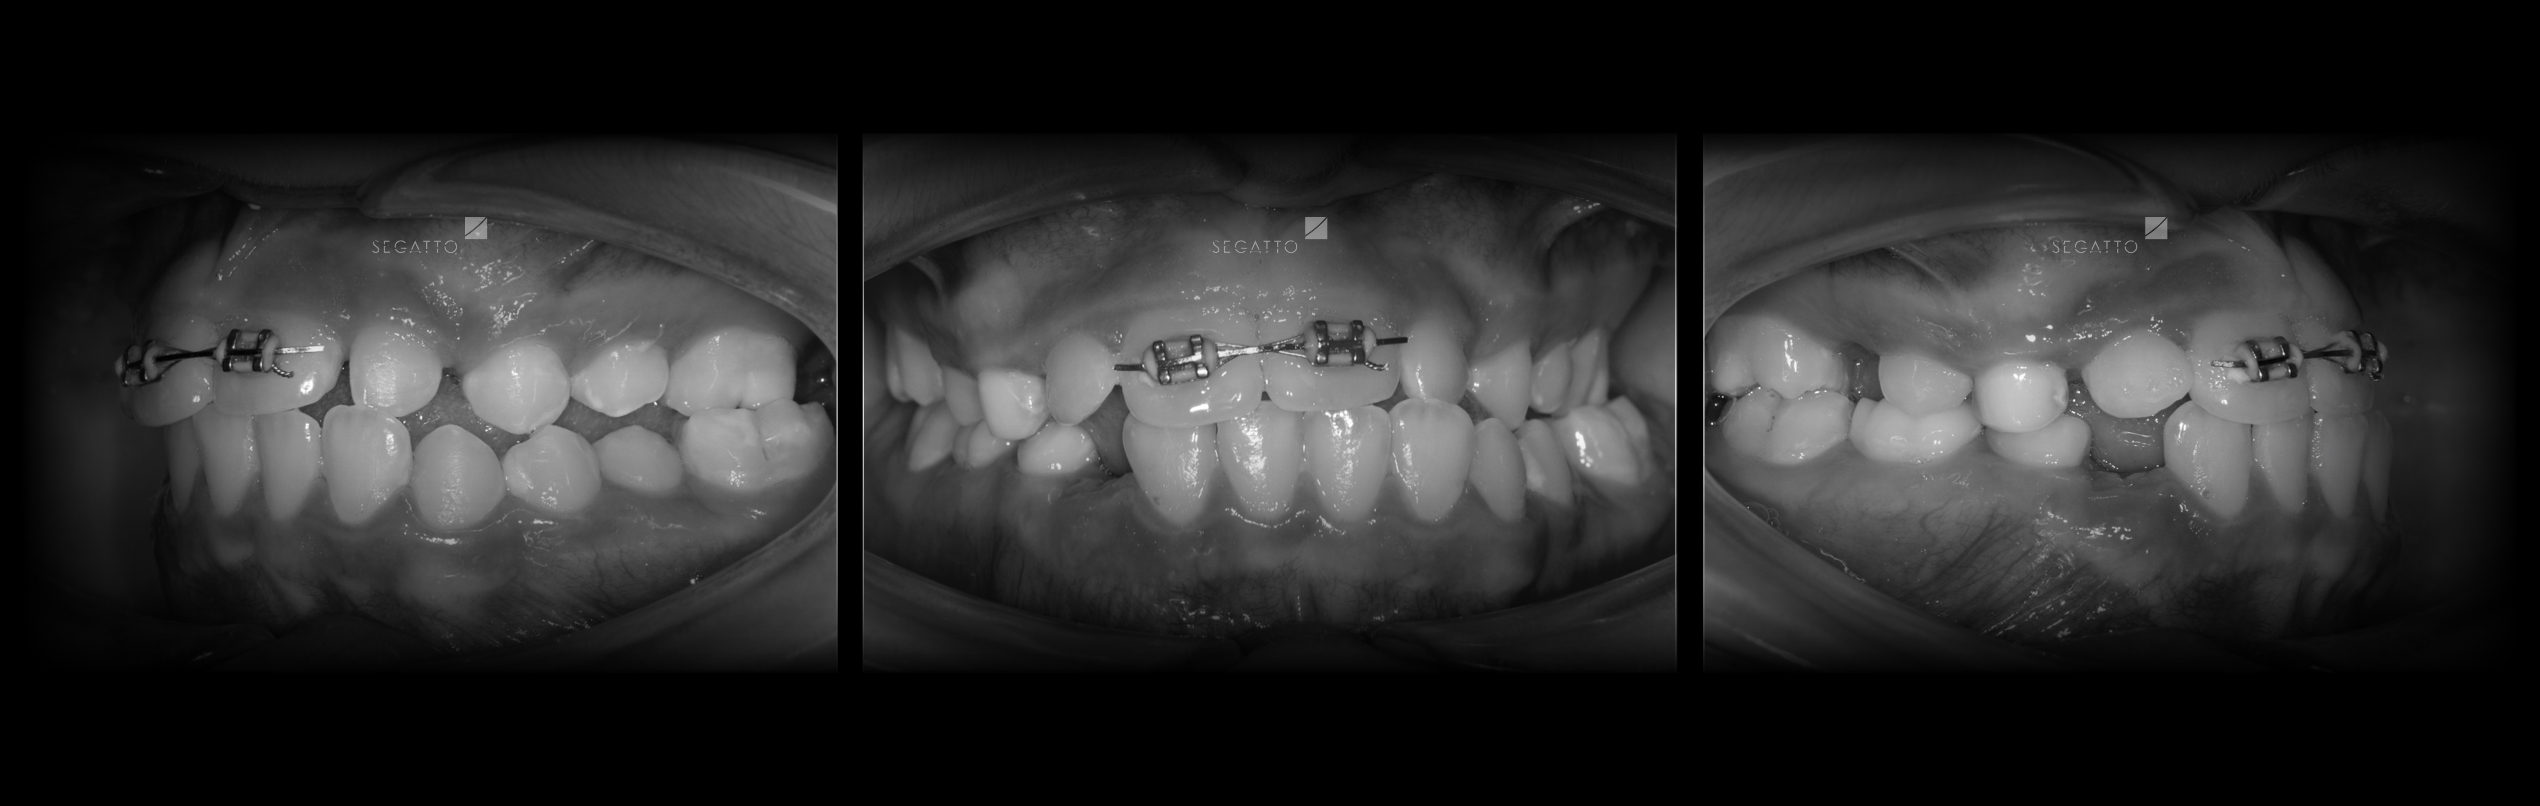

Orthodontics

Cases